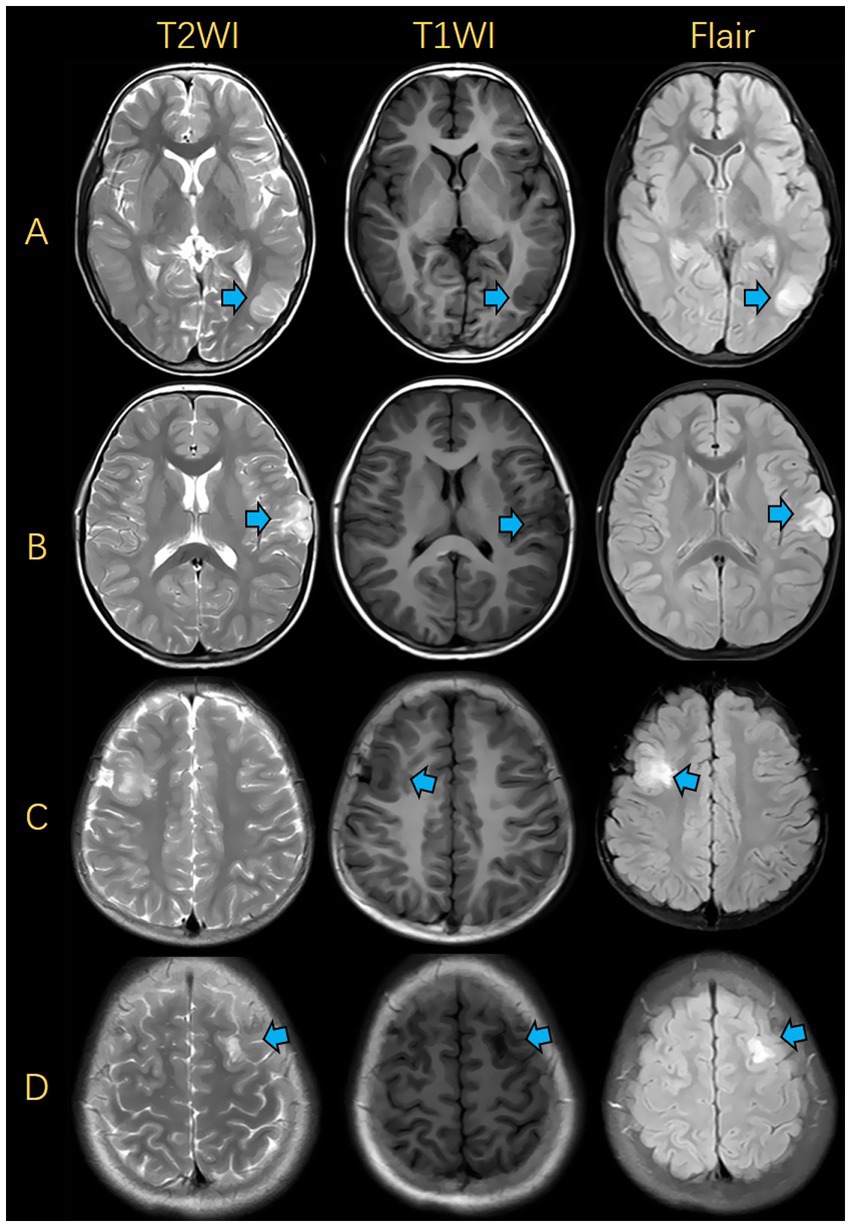

The accuracy, sensitivity and specificity of the junior radiologist’s assessment were50.0, 53.6, and 45.5%, respectively, while those of the senior radiologist’s assessment were 76.0, 78.6, and 72.7%, respectively. The diagnostic performance of the fusion radiomics model was superior to that of the junior radiologist and comparable to that of the senior radiologist (Table 2). During radiologists reading, there were some easily-confused cases, which led to misdiagnosis. The representative FCD and DNET cases with similar imaging findings are shown in Figure 5.

Figure 5

Illustrations of MRIs for FCD and DNET. (A) FCD was presented in the left occipital lobe. (B) DNET was presented in the left frontal lobe. (C) FCD was presented in the right frontal lobe. (D) DNET was presented in the left frontal lobe. FCD, focal cortical dysplasia; DNET, dysembryoplastic neuroepithelial tumors.